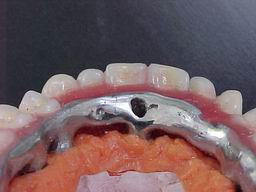

Enceramento prévio para confecção da barra fundida (Protocolo Inferior):

Vista oclusal da "Protocolo" antes da acrilização Superior: Prova de montagem em cera      sobre barra fundida.